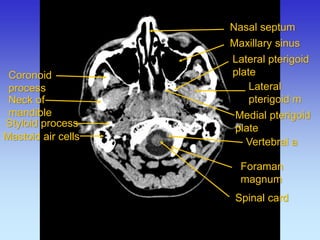

Coronoid process

Neck of mandible

Lateral pterigoid m

Lateral pterigoid plate

Medial pterigoid plate

Maxillary sinus

Nasal septum

Mastoid air cells

Styloid process

Spinal card

Foraman magnum

Vertebral a